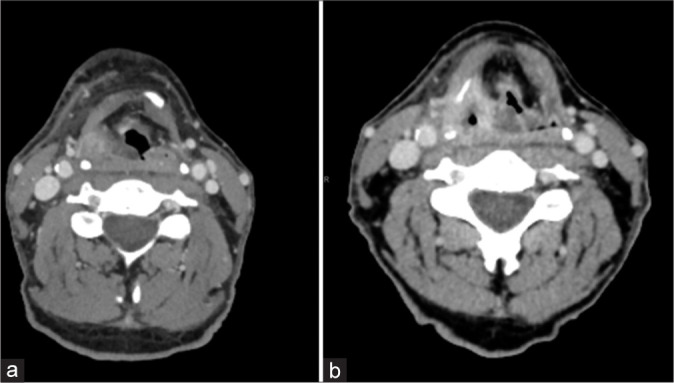

本综述描述了头颈癌(HNCs)急诊病例的放射学表现,包括未确诊和曾接受治疗的患者,重点强调了每次表现的时间紧迫性,以及与相关临床表现和必要治疗的联系,以加强理解和认识。HNC的各种表现将根据其主诉的器官系统来描述。我们将详细介绍每一种疾病的发展和并发症,重点介绍急诊科的临床表现和对诊断至关重要的影像学结果。每个报告将与一个特定的病例一起展示,并展示所获得的精确的计算机断层扫描、磁共振成像、超声或数字减影血管造影图像。病例包括声门肿瘤或转移性颈部淋巴结病引起的气道阻塞;手术并发症血肿或放疗后软组织水肿引起的气道阻塞;肿瘤或淋巴结压迫、颈动脉爆裂、颈动脉狭窄或闭塞等血管并发症;眶间室综合征并发症;骨髓炎和骨放射性坏死的骨科并发症。11例HNC患者与其相关的32张图像。HNC患者在紧急情况下表现出具有挑战性的影像学特征。辨别正确诊断的困难来自复杂的头颈部解剖结构,通常由于出现的晚期和功能状态差而复杂化。放射科医师熟悉常见的HNC急诊表现对于准确诊断和及时治疗至关重要。

This review describes the radiographic findings in emergencies of head and neck cancers (HNCs) in both undiagnosed and previously treated patients, with an emphasis on the temporal urgency of each presentation and in association with the relevant clinical presentation and necessary treatments to enhance understanding and recognition. The various presentations of HNC will be described by the organ system of their presenting complaint. The development and complications of each will be elaborated, with a focus on the clinical presentation in the emergency department and the imaging findings that are critical to recognize in making the diagnosis. Each presentation will be exhibited with a specific patient case and the exact computed tomography, magnetic resonance imaging, ultrasound, or digital subtraction angiography images obtained will be shown. Cases include airway obstruction due to glottic tumor or metastatic cervical lymphadenopathy; airway obstruction due to surgical complications of hematoma, or post-radiation soft-tissue edema; vascular complications of tumor or nodal compression, carotid blowout, carotid stenosis, or occlusion; orbital complications of compartment syndrome; and orthopedic complications of osteomyelitis and osteoradionecrosis. Eleven HNC patient cases are presented with their associated 32 images. HNC patients present with challenging imaging features in the emergent setting. Difficulty in discerning the correct diagnosis arises from the complex head and neck anatomy, often compounded by an advanced stage at presentation and poor functional status. Radiologist familiarity with common HNC emergent presentations is essential for accurate diagnosis and timely treatment.